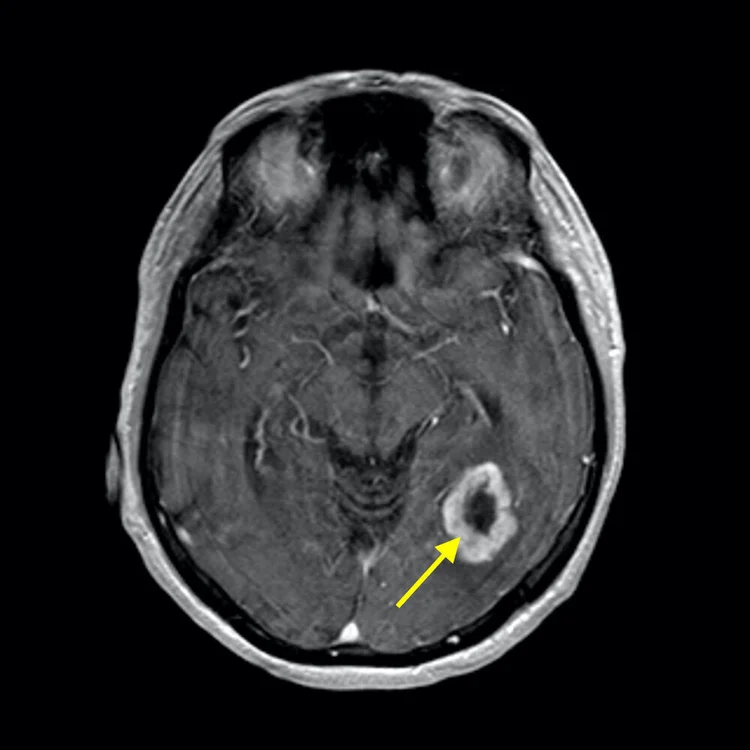

Glioblastoma (GBM) is the most aggressive and common form of primary malignant brain tumor in adults. GBM arises from glial cells—specifically astrocytes—which normally support and protect neurons in the brain. Classified as a Grade IV tumor by the World Health Organization, glioblastoma is characterized by rapid growth, high invasiveness, and a strong resistance to most conventional therapies.

One of the defining features of glioblastoma is its ability to infiltrate surrounding brain tissue. Unlike many other cancers that form well-defined masses, GBM spreads in a diffuse, finger-like pattern, making it nearly impossible to remove completely through surgery. Even when imaging suggests a successful resection, microscopic tumor cells almost always remain, leading to recurrence.